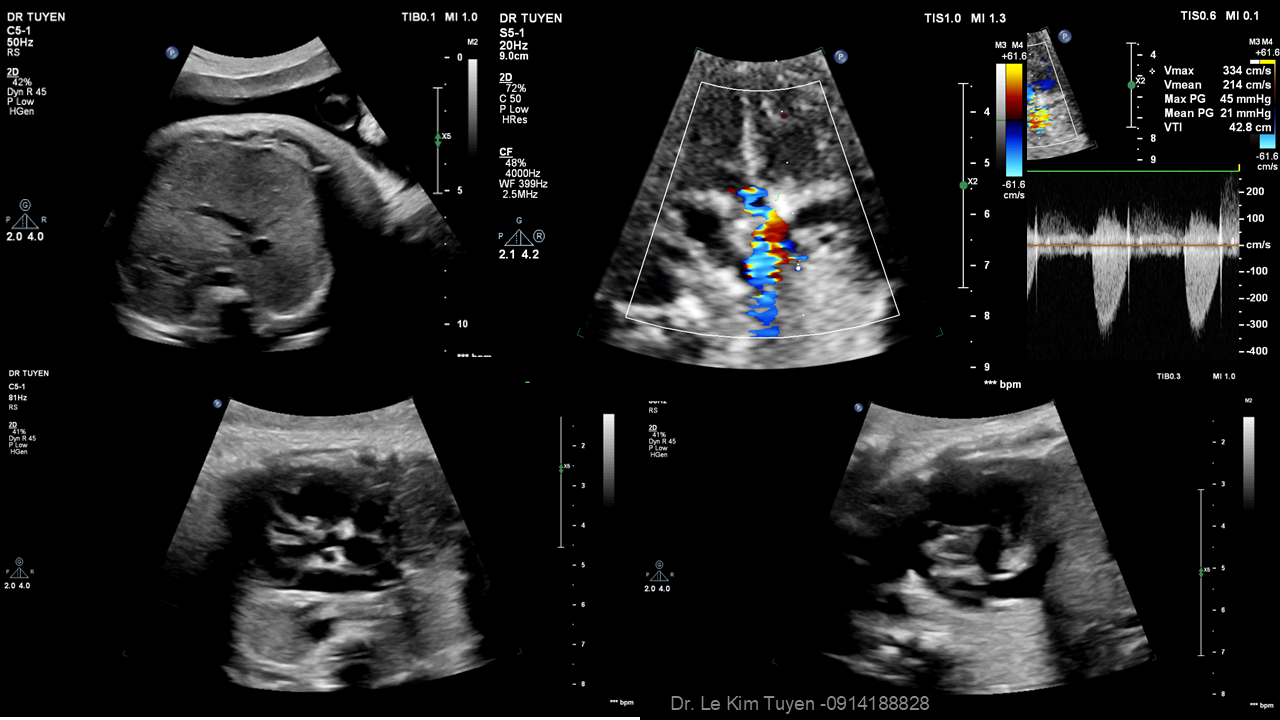

Áp dụng công nghệ Graphicflow trong phát hiện bệnh tim bẩm sinh cần cấp cứu sơ sinh

TS. BS. Lê Kim Tuyến

Bệnh viện Tim Tâm Đức